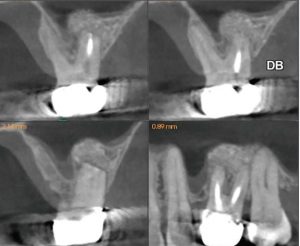

The patient was referred for a CBCT; the scan (Figure 5)

revealed a common area of rarefying osteitis surrounding the mesial buccal and distal buccal roots which had caused elevation of the sinus floor. As the endodontic pathology had not resolved, treatment options were proposed. The patient chose to have microsurgical therapy performed.